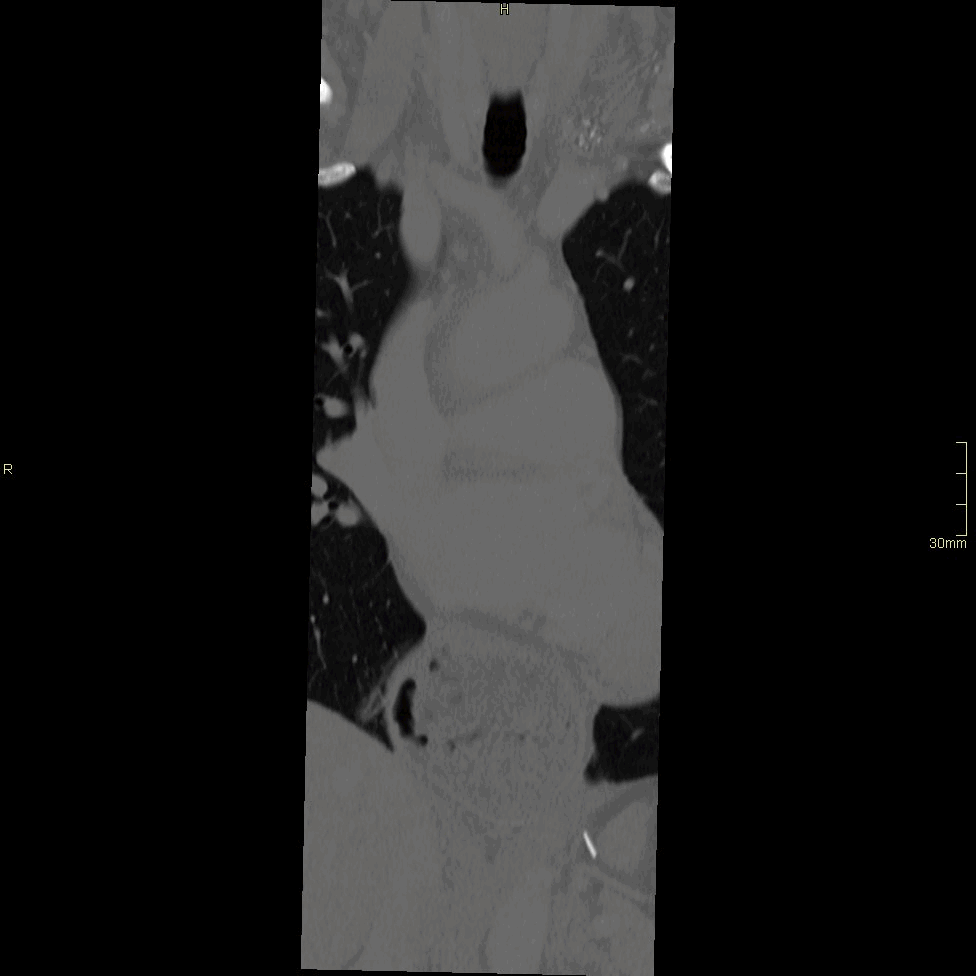

CT Thoracic Spine Contrast- Soft tissue window (axial)

CT Thoracic Spine Contrast- Soft tissue window (coronal)

CT Thoracic Spine Contrast- Soft tissue window (sagittal)

CT Thoracic Spine Contrast- Bone window (axial)

CT Thoracic Spine Contrast- Bone window (coronal)

CT Thoracic Spine Contrast- Bone window (sagittal)